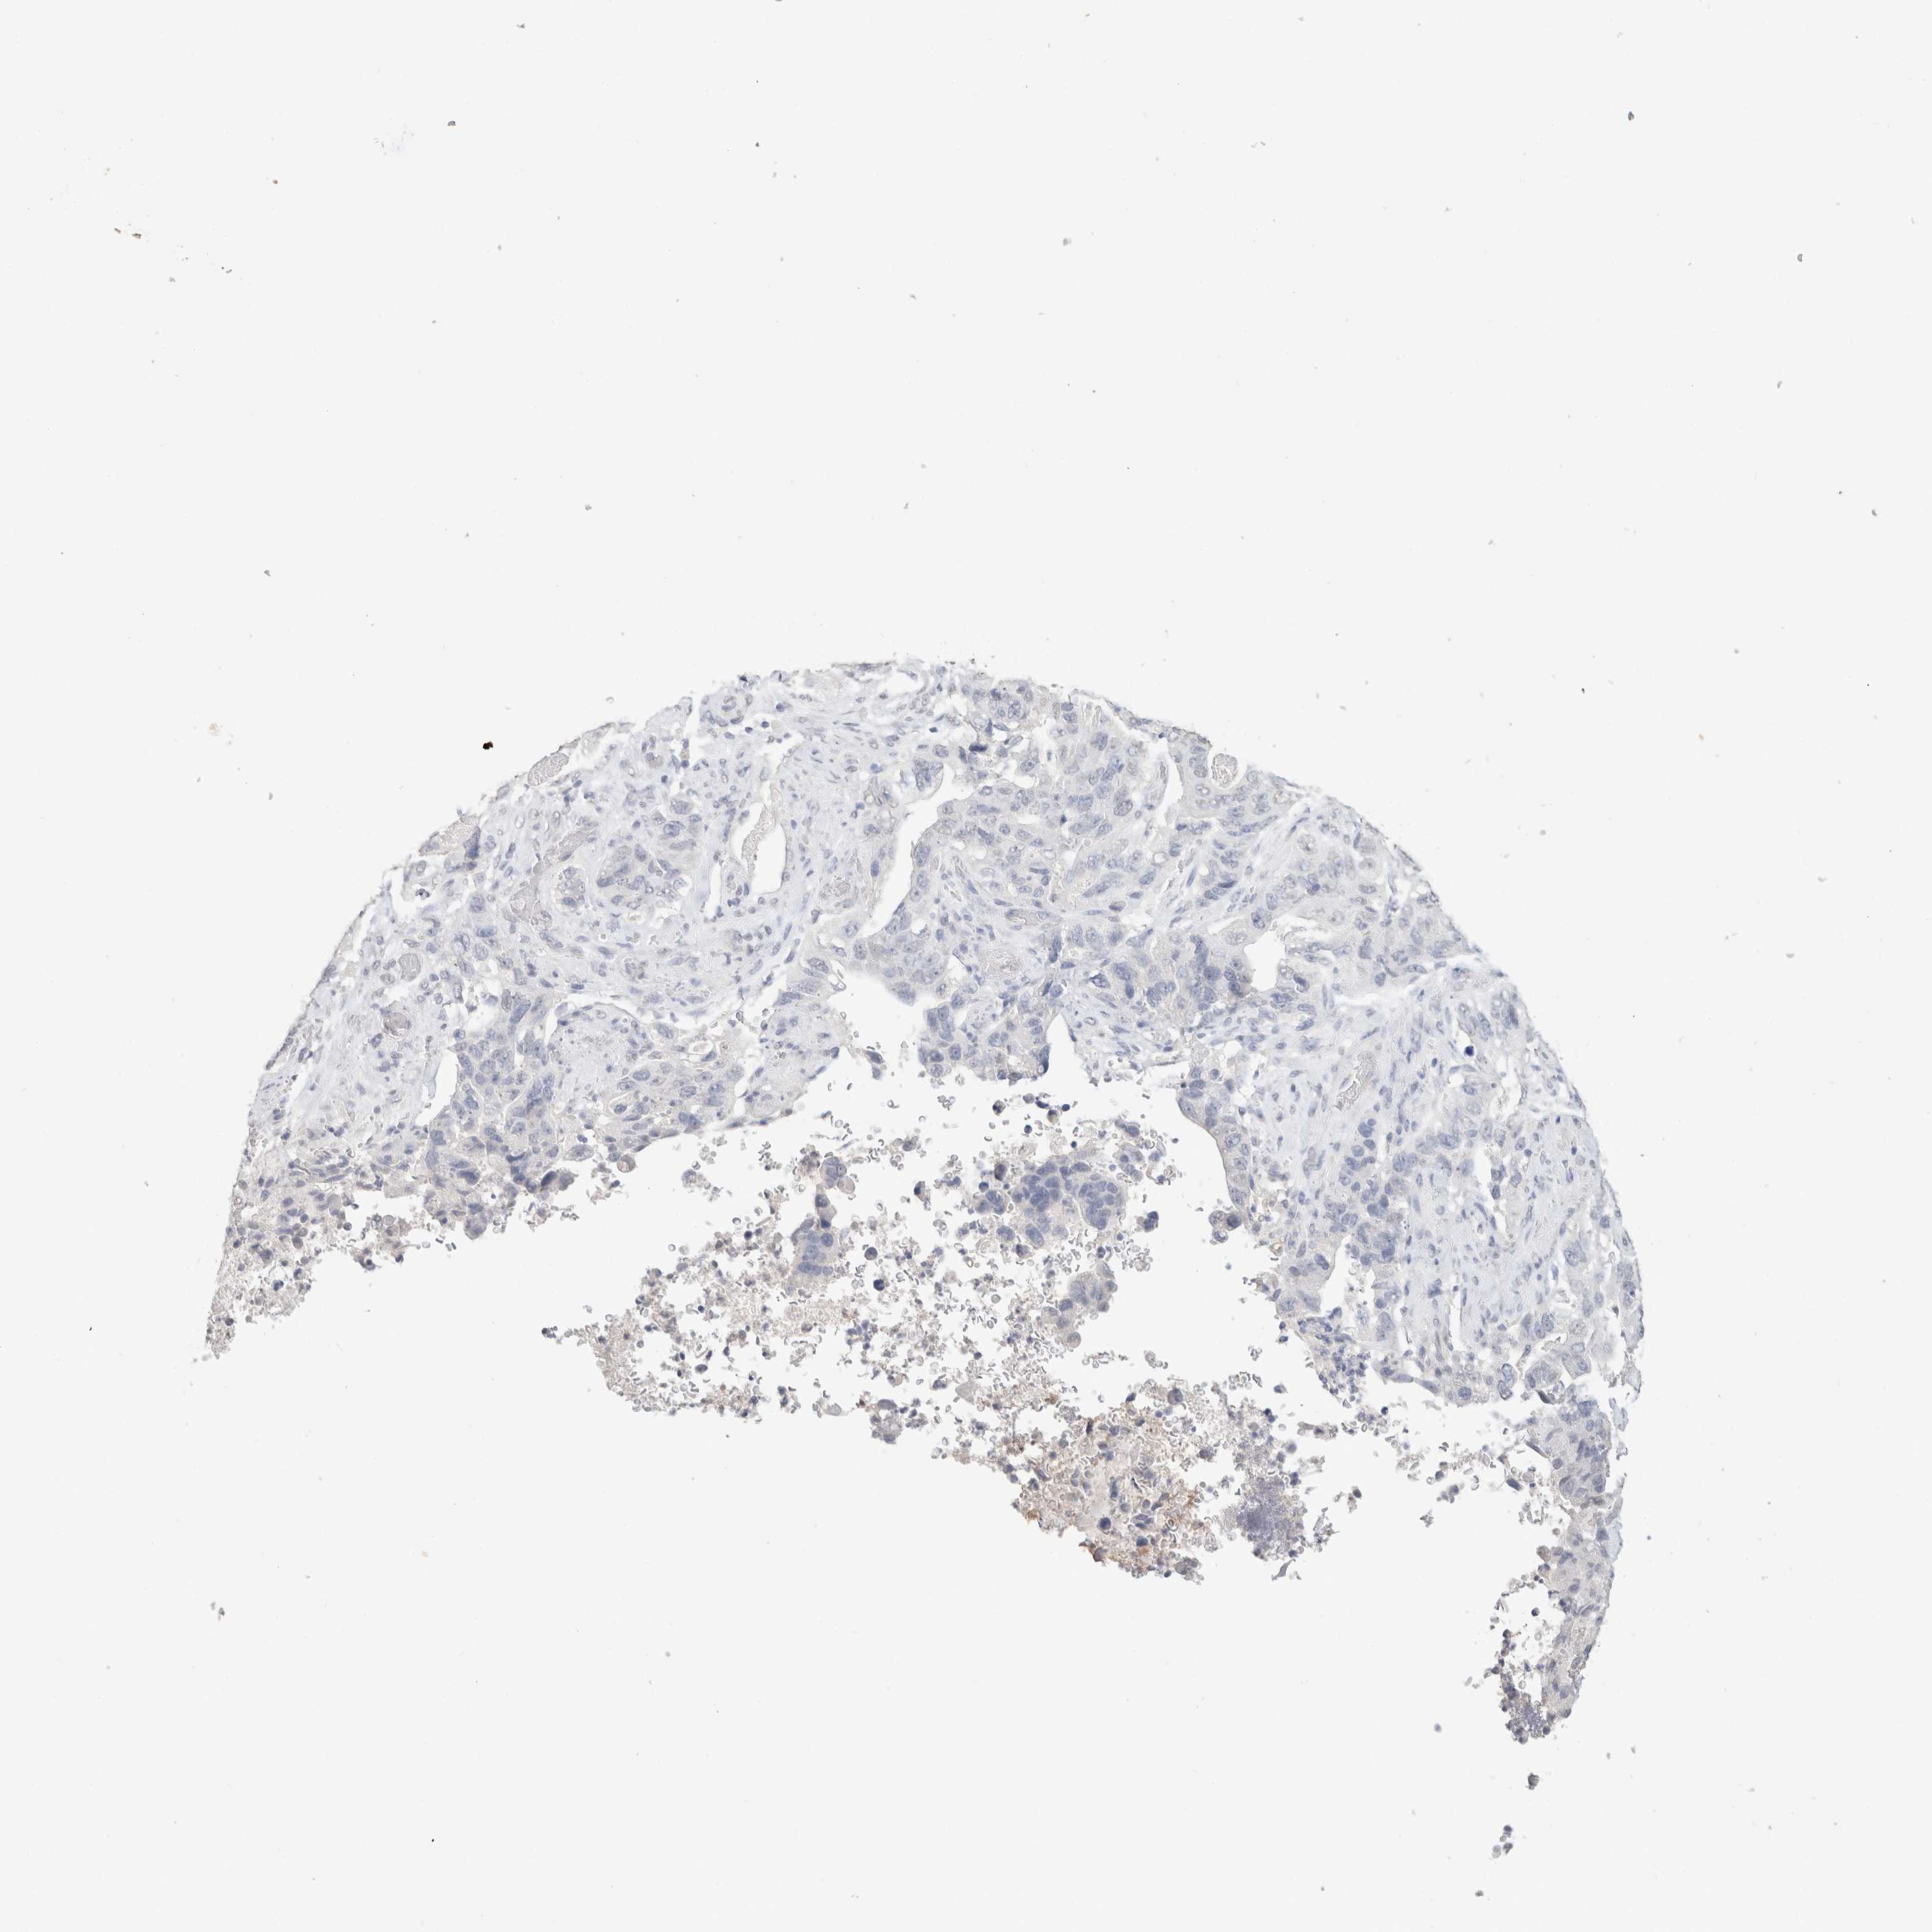

STOMACH CANCER - Protein expressioni

A mouse-over function shows sample information and annotation data. Click on an image to view it in a full screen mode. Samples can be filtered based on level of antibody staining by selecting one or several of the following categories: high, medium, low and not detected. The assay and annotation is described here.

Note that samples used for immunohistochemistry by the Human Protein Atlas do not correspond to samples in the TCGA dataset.

Antibody stainingi

Antibody staining in the annotated cell types in the current human tissue is reported as not detected, low, medium, or high, based on conventional immunohistochemistry profiling in selected tissues. This score is based on the combination of the staining intensity and fraction of stained cells.

Each image is clickable and will lead to virtual microscopy that enables deeper exploration of all samples and also displays staining intensity scores, fraction scores and subcellular localization as well as patient and tissue information for each sample.

Antibody HPA050092

Antibody CAB025368

Staining

High

Medium

Low

Not detected

Intensity

Strong

Moderate

Weak

Negative

Quantity

>75%

75%-25%

<25%

None

Location

Nuclear

Cytoplasmic/membranous

Cytoplasmic/membranous,nuclear

Adenocarcinoma, NOS

Adenocarcinoma, High grade